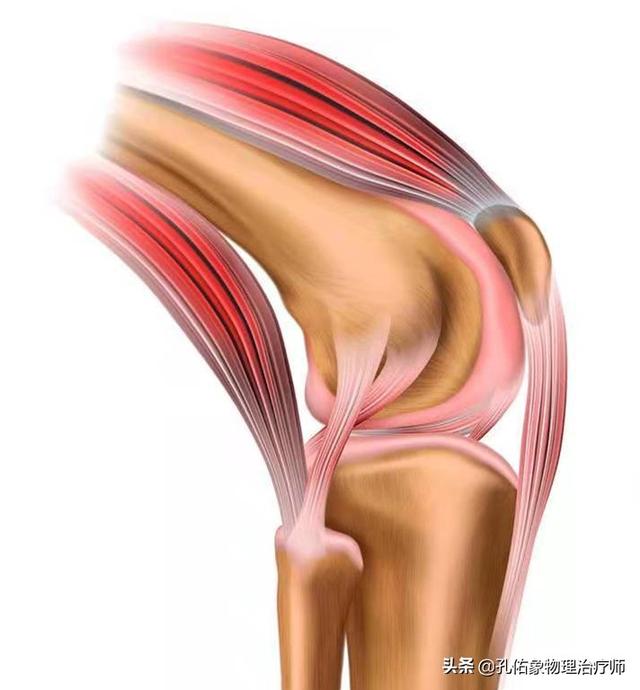

Sur la surface des os de l'articulation du genou, il y a une couche de cartilage attachée, généralement dans l'articulation du genou sous une charge de pression excessive, ce sera à cause de l'usure du cartilage, dans nos activités, montrant la douleur ; l'usure du cartilage progressivement aggravée, conduira à l'os de la cuisse et l'os du mollet collision dure, la perte de la stabilité de l'articulation, et progressivement il y a ostéomalacie, la détérioration de la circulation sanguine, le refroidissement et le bruit d'éclatement est inévitable.

L'articulation du genou comporte deux ménisques, l'un médial et l'autre latéral. Le ménisque médial est relié au ligament collatéral médial et à la capsule articulaire médiale, tandis que le ménisque latéral est relié à la capsule articulaire latérale ; le quadriceps, le muscle semi-membraneux et le muscle poplité, à l'arrière, sont également reliés au ménisque. Le ménisque est une structure très importante de notre corps, qui non seulement approfondit la profondeur de la fosse articulaire, rend la connexion entre l'os de la cuisse et l'os du mollet plus adaptable et augmente la stabilité de l'articulation du genou, mais protège également l'articulation du genou et agit comme un coussin pour amortir les chocs.

Cependant, dans la vie de tous les jours, lesLe ménisque est souvent négligé, mais les douleurs du genou y sont liées d'une manière ou d'une autre !. Pour mieux le connaître, il faut aussi connaître l'apport nutritionnel du ménisque :

Le ménisque s'appuie fortement sursang和liquide synovial dans la capsule articulaire (médecine)Deux substances principales sont fournies : le tiers externe du ménisque est irrigué par le sang et une petite partie est située au centre, tandis que le tiers interne est dépourvu de sang et dépend principalement du liquide synovial de la capsule articulaire pour son alimentation.

Si le ménisque a dégénéré, il peut être endommagé lorsque vous vous accroupissez par inadvertance ou lorsque vous vous levez et faites pivoter votre corps. Il est évident que les problèmes d'irrigation sanguine, d'amortissement et de liquide synovial contribuent directement à la froideur, à la douleur et au cliquetis que vous ressentez lorsque vous bougez.

La maladie ne concerne pas seulement les os, les articulations et le cartilage articulaire, mais aussi les tendons, les ligaments et les rotules autour de l'articulation du genou, qui sont irrités par la tension et l'inflammation, ce qui provoque des douleurs et une gêne.